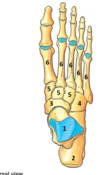

Perfectly

8

Q

L5 lesion features

A

loss of foot dorsiflexion + sensory loss dorsum of the foot

How well did you know this?